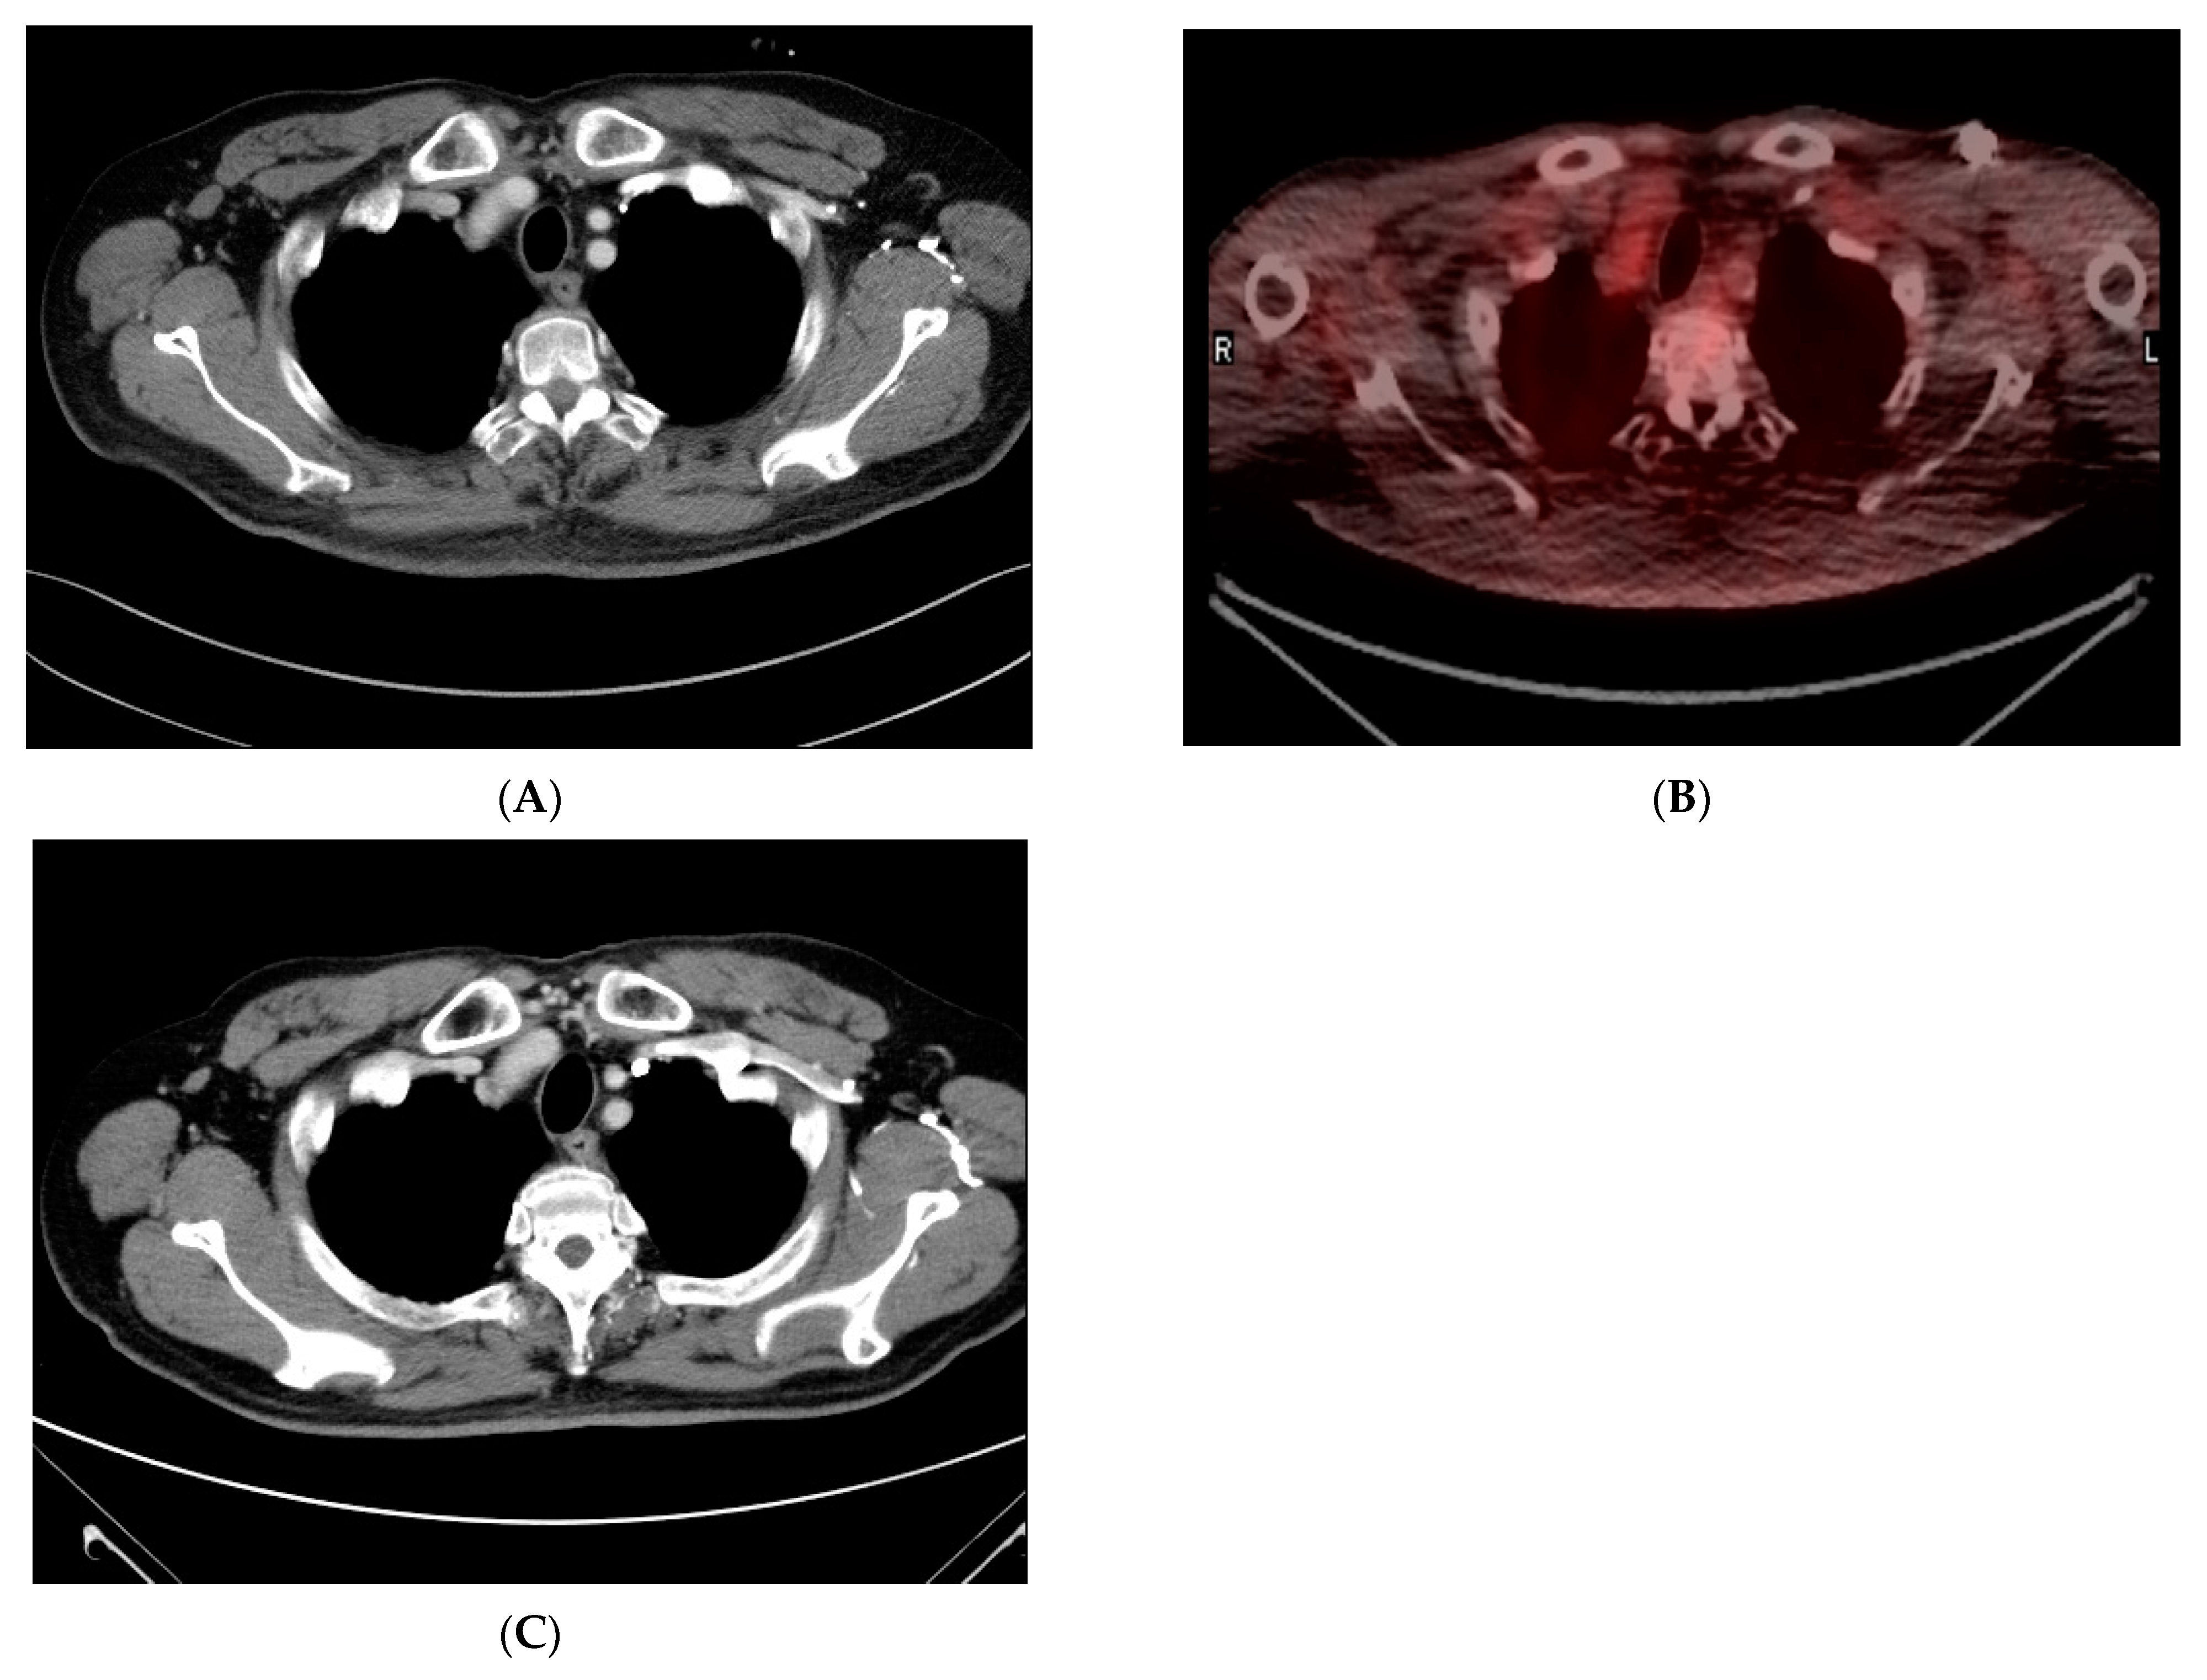

2. Case Report